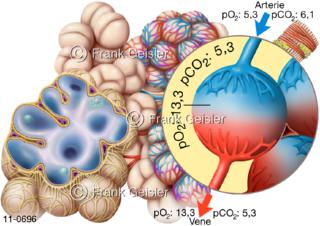

11-0696 Lobulus der Lunge mit Lungenbläschen Alveolen, Alveolus-Partialdruck